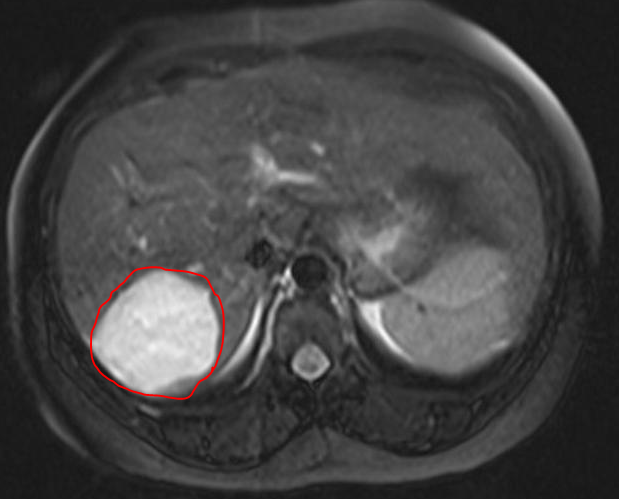

2. CT Scan or MRI Scan